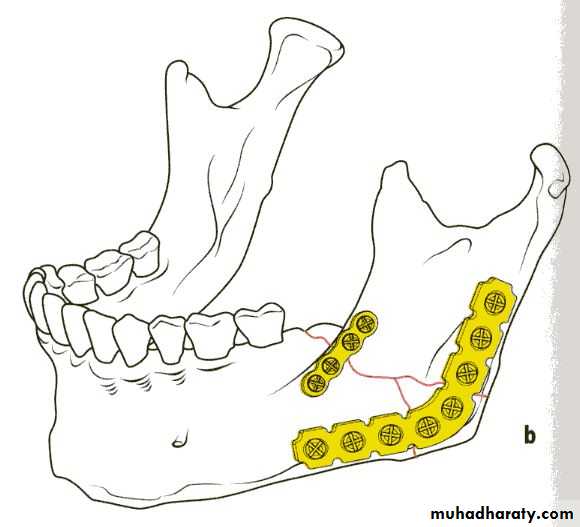

Plating

If teeth are present IMF is done ; then incision is made and bone is reached either extra orally or intra orally.The fractured ends are approximated and screw holes are made such that at least 2 screws can be placed on either side of the fracture.

The champy,s technique of plate fixation

1- Use mono cortical screw fixation ; place a minimum of 2 screws on each side of the fracture.2- The more posterior the fracture the more higher the plate should be placed . The more anterior the fracture , the closer the plate should be placed to the lower border.

3-To avoid devitalization of bone , place plates supra periosteally in atrophic edentulous mandible and extensively comminuted fracture.

In plating posterior mandible single upper border plate is enough for fixation. While in plating anterior mandible , two plates are required to help counter the torsional forces of fracture in this location.